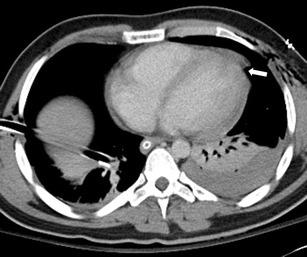

Thoracic injuries are the third most common injuries in trauma patients with cardiac injuries amongst the most lethal. Imaging is essential in diagnosis and triage of patients with pericardial injuries, and this review aims to highlight the spectrum of imaging findings of pericardial trauma. Focussed assessment with sonography for trauma (FAST) is the preferred initial examination, being rapid and accurate. Sensitivity of FAST for pericardial fluid detection is high with reported sensitivities of 97-100%. Plain chest radiography has low sensitivity for pericardial injuries but is useful in the evaluation of associated injuries. Computed tomography (CT) is the modality of choice for stable patients and can accurately diagnose traumatic pathology of the pericardium being especially useful in identification of cardiac herniation. The spectrum of CT findings includes pericardial fluid collections, focal pericardial defects and pneumopericardium.

A selection of cases of pericardial trauma encountered at a level one trauma centre is presented. Operative findings were correlated with the FAST scan, plain radiography and computed tomography imaging.

The imaging findings of pericardial trauma with various imaging modalities (ultrasound, plain radiography and computed tomography) are presented in order to aid interpretation during the acute trauma setting.